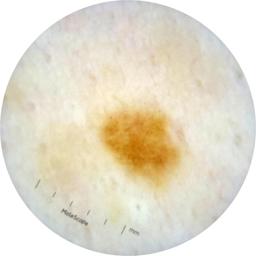

ISIC_9472333

acquisition_day 230

age_approx 65

anatom_site_1 Trunk

anatom_site_2 Anterior trunk

anatom_site_general anterior torso

diagnosis_1 Benign

diagnosis_confirm_type single image expert consensus

family_hx_mm True

fitzpatrick_skin_type I

image_manipulation instrument only

image_type dermoscopic

personal_hx_mm True

sex female